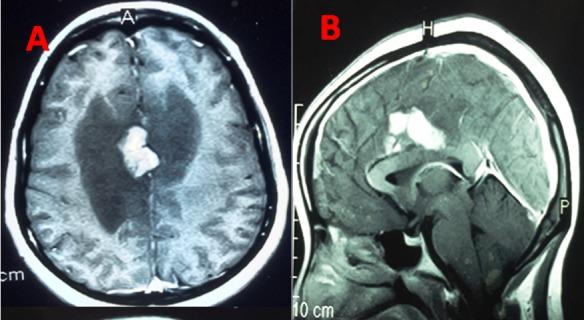

Tuberculosis is a major public health problem in developing countries. Cerebral tuberculomas is a tuberculous granulation tissue mass restrained and limited by immune defenses of the host. This study aims to describe the characteristics and the evolutionary profile of intracranial tuberculomas in Mauritania. Data of 34 patients with intracranial tuberculoma were collected retrospectively in several hospitals in the city of Nouakchott between January 2005 and June 2017. Evolutionary features of patients under treatment were analyzed. Our retrospective study involved 20 men and 14 women (sex ratio 1.4). The average age of our patients was 28.7 years. Twelve patients were less than or equal to 16 years. Symptomatology was dominated by increased intracranial pressure and seizures in 27 cases (79.41%) and 20 cases (58.82%) respectively. Intradermo tuberculin reaction was positive in 14 (41.17%) cases. Supratentorial lesion was found in 24 patients (70.58%). In all patients, therapeutic approach was based on multidrug chemotherapy for a period greater than or equal to 12 months. Surgical procedure was performed in 12 patients (35.29%). Outcome was favorable with complete healing without sequelae in 23 cases, reflecting a rate of 67.64%. Given the non-specific role of imaging exams in the diagnosis of intracranial tuberculoma and the lack of the stereotactic biopsy in our Country where the disease is endemic, we recommend to perform a two-month therapeutic test in patients with suspicious lesions.

结核病是发展中国家的一个主要公共卫生问题。脑结核瘤是一种受宿主免疫防御限制和局限的结核性肉芽组织肿块。本研究旨在描述毛里塔尼亚颅内结核瘤的特征和演变情况。2005年1月至2017年6月期间,在努瓦克肖特市的几家医院对34例颅内结核瘤患者的数据进行了回顾性收集。分析了接受治疗患者的演变特征。我们的回顾性研究纳入了20名男性和14名女性(性别比为1.4)。患者的平均年龄为28.7岁。12名患者年龄小于或等于16岁。症状以颅内压升高和癫痫发作为主,分别有27例(79.41%)和20例(58.82%)。结核菌素皮内反应阳性的有14例(41.17%)。幕上病变见于24例患者(70.58%)。所有患者的治疗方法均为多药化疗,疗程大于或等于12个月。12例患者(35.29%)接受了手术治疗。23例患者预后良好,完全愈合且无后遗症,愈合率为67.64%。鉴于影像学检查在颅内结核瘤诊断中的非特异性作用,以及在我们这个疾病流行的国家缺乏立体定向活检,我们建议对可疑病变患者进行为期两个月的治疗性试验。